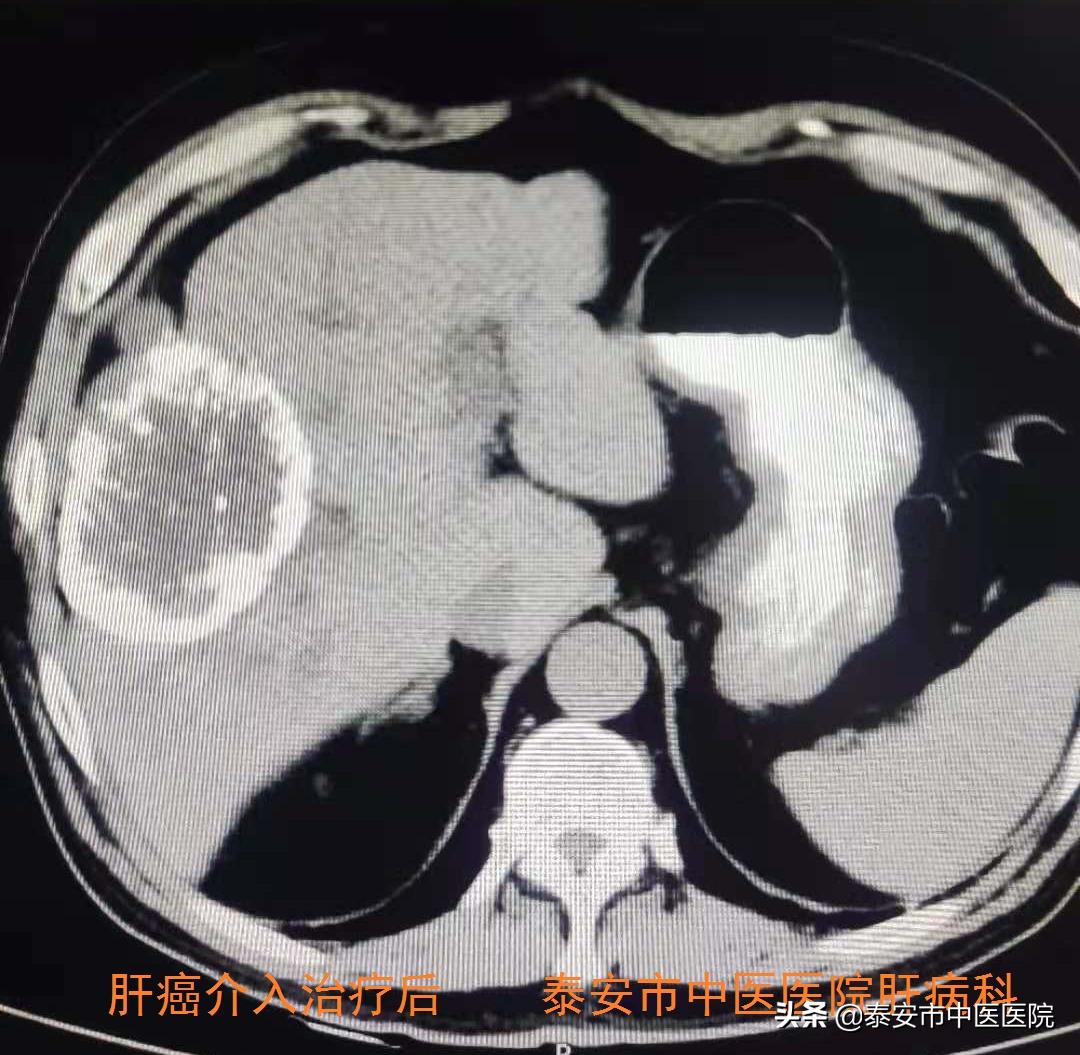

3.肝癌介入治疗

借助医院引进的Philips最新一代霓彩系列大平板数字减影血管造影机(DSA),与介入科合作开展肝癌介入治疗。在数字减影血管造影机下,超选择插管至肿瘤供养血管内,进行肝动脉灌注化疗(TAI)、肝动脉栓塞(TAE)、肝动脉化疗栓塞(TACE)等治疗,是控制肝癌生长及联合系统治疗的主要手段之一。